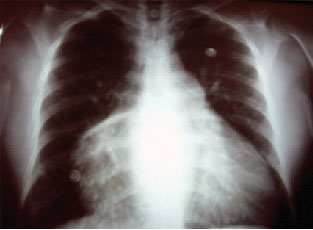

El padecimiento lo inicia con disnea de grandes esfuerzos de 1 año de evolución, para posteriormente debutar con disnea de pequeños esfuerzos, ortopnea, así como disnea paroxística nocturna, acompañada de tos productiva, con expectoración hialina en escasa cantidad, emesis en dos ocasiones, insomnio, astenia, adinamia y pérdida de peso. En la exploración física, con edad mayor a la cronológica, consciente, actitud endomórfica, constitución hipotrófica, fascies inespecífica, palidez de piel y tegumentos, regular estado hídrico; TA: 90/60 mm Hg, FC: 60 lat/min, Temp: 36.5 °C. Con ingurgitación yugular G II, aumento de los movimientos respiratorios, con rudeza respiratoria bilateral, ruidos cardiacos rítmicos con soplo diastólico mitral II/ IV, borde hepático rebasa 5 cm el reborde costal, dolor a la palpación en hipocondrio derecho. Exámenes de laboratorio: HB de10 mg/dL, glucosa 95 mg/dL, Na 140, K 4.5, leucocitos 10 900, neutrófilos 12 500, RX de tórax: cardiomegalia grado IV, aurícula izquierda dilatada, con cuarto arco izquierdo de la silueta cardiaca, cefalización de flujo (figura 2). ECG: eje eléctrico 45°, ritmo sinusal, crecimiento auricular izquierda, no isquemia, lesión o necrosis. ECO TT: aurícula izquierda dilatada, tumor de aurícula izquierda 40x40 mm, fijo al septum interatrial izquierdo, protruye a la válvula mitral, con HAP 30 mm Hg, insuficiencia triscupídea leve a moderada, FEVI 54%. Se somete a sesión médico-quirúrgica y se programa para resección de tumor intracardiaco y revisión de válvula tricuspídea por esternotomía media estándar, con los siguientes hallazgos: cardiomegalia III, aurícula izquierda de 49x38 mm de diámetro con pedículo a nivel del septum intraarterial izquierdo que protruye a válvula mitral, de aproximadamente 80x90 mm de diámetro (figura 3).